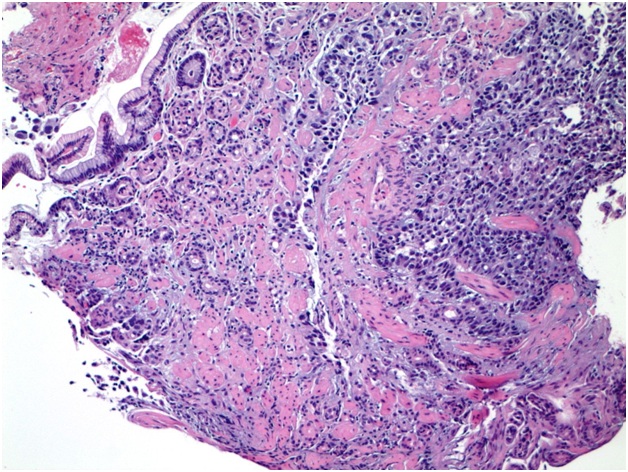

Acinar Cell Carcinoma of the Pancreas with Gastric Metastasis: A Case Report and Literature Review